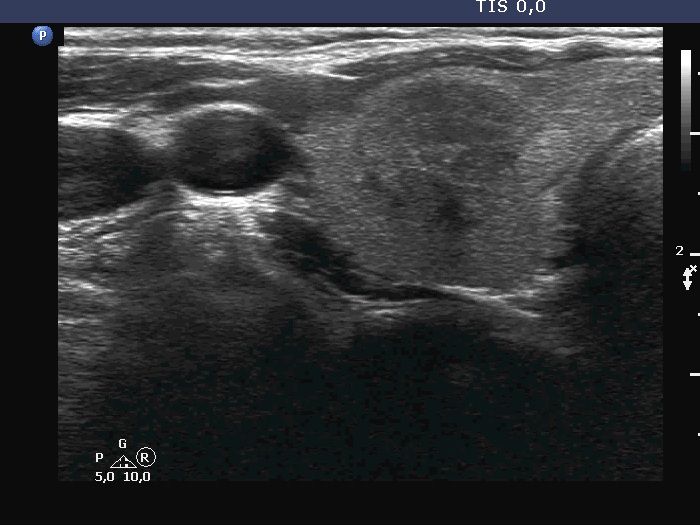

Ultrasonography. The thyroid was echonormal. There were three discrete lesions in the right lobe while several others in the left lobe. There was only one remarkable among them. This was in the ventral part of the right lobe. It was minimally hypoechoic, presented with partly irregular, partly blurred borders. Intranodular vascularity was detected.